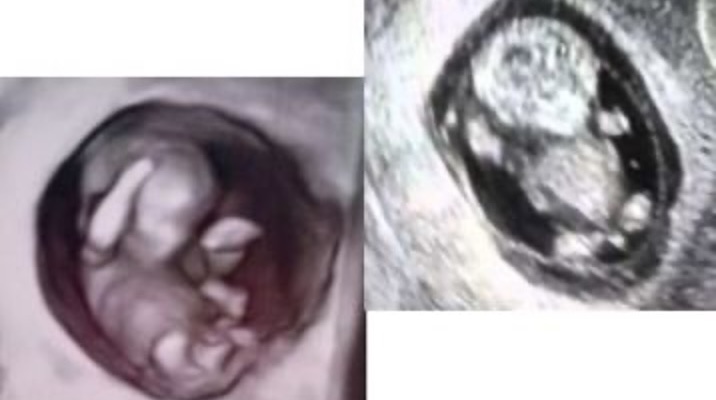

「お口ぽかん」の原因は、 胎児がお腹の中いる時から始まっていると考えられます。下の写真をご覧ください。このふたつの写真の違いは何でしょうか。

これは、 赤ちゃんが子宮内にいる時のエコー 写真です。まるい子宮にいる赤ちゃんと、少々歪んでいる子宮にいる赤ちゃん、どちらが成長にとって良い環境なのかは、想像がつきます。当然、お口もこの環境下で育ちます。これが、「生まれつき」の正体の一つです。

居心地の良いまるい子宮で育った赤ちゃんと、少し窮屈な子宮で育った赤ちゃんのお口の違いが下の写真です。